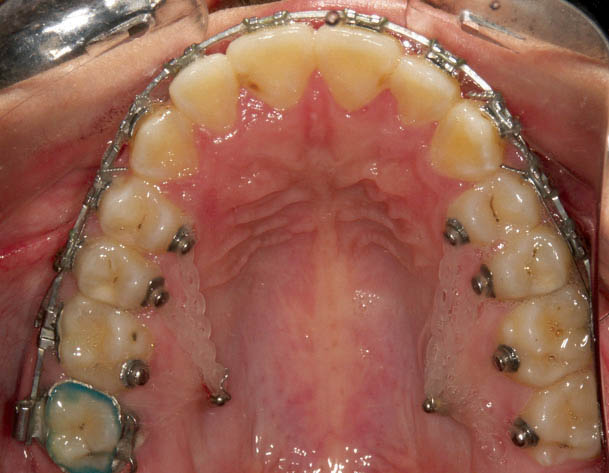

شکل 221-1: برای اینترود کردن سگمنت خلفی در بیماران اپنبایت به دو مینی اسکرو در سمت باکال و پالاتال همزمان نیاز است.